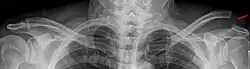

Schultereckgelenksprengung Tossy 3 in der Panoramaaufnahme des Schultergürtels mit Belastung.

Zur Standarddiagnostik wird ein Röntgen in drei Ebenen durchgeführt. Die axiale Aufnahme dient dabei der Feststellung eines horizontalen Translation (Rockwood 4). In Zweifelsfällen werden Aufnahmen von beiden Schultern zum Vergleich angefertigt. Dies kann als eine Panoramaaufnahme des gesamten Schultergürtels erfolgen. Hierbei ist die Untersuchung mit Gewichten (5 bis 10 kg) an den Handgelenken sensitiver als Aufnahmen ohne. Diese Untersuchung spielt aufgrund der Strahlenbelastung zunehmend eine untergeordnete Rolle.